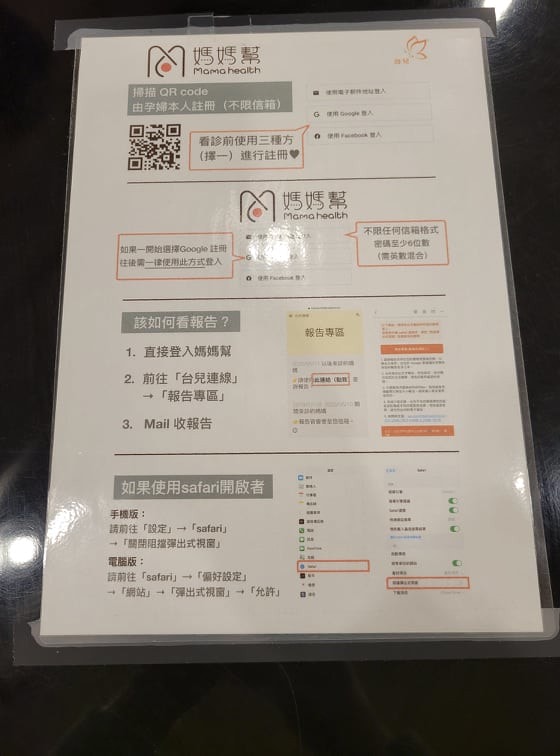

喔對~~~一到台兒他們會先讓你下一個APP

產檢和各項檢查都能透過他們的app直接下載照片

超音波的照片跟報告結果

在上面直接看得到唷

幾乎是一走出去看得到結果

所以很快耶!!!!